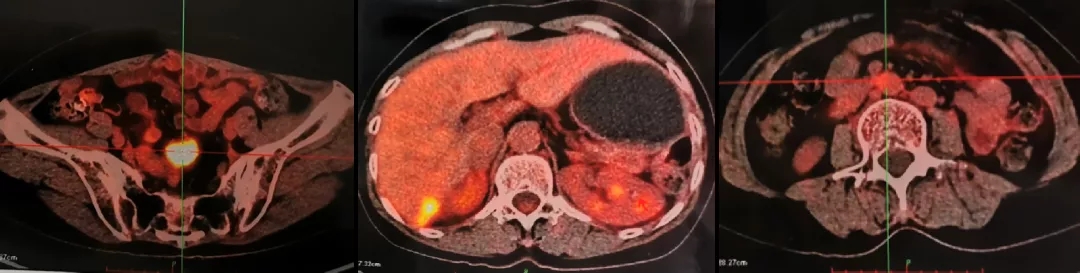

2016.10.14查PET-CT: 盆腔内软组织密度灶,FDG代谢异常增高,考虑转移灶;右肝后下段包膜处结节样、片状转移灶;左肾前方斑片状,腹主动脉管壁处(L3椎体水平)FDG代谢轻度增高,考虑肿瘤活性组织存在。

PET-CT检查结果